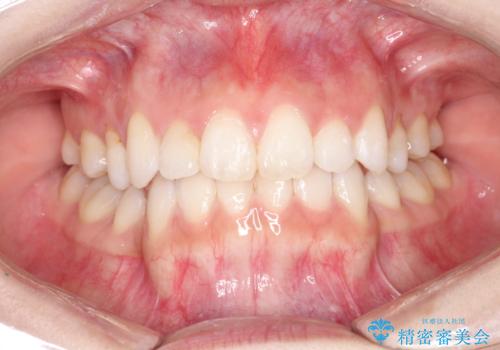

前歯の後戻りを部分矯正で整った歯並びへ